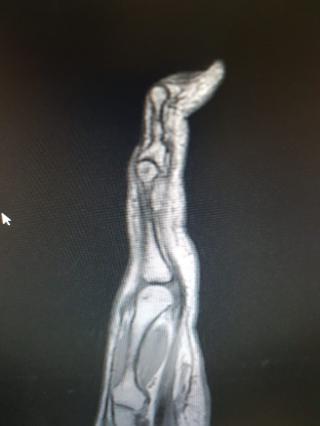

Мужчина 7 лет назад упал с мотоцикла. 4 и 5 палец практически не работают. Выраженный артроз мелких суставов кисти. После операции: движения в полном объеме. Болей нет.